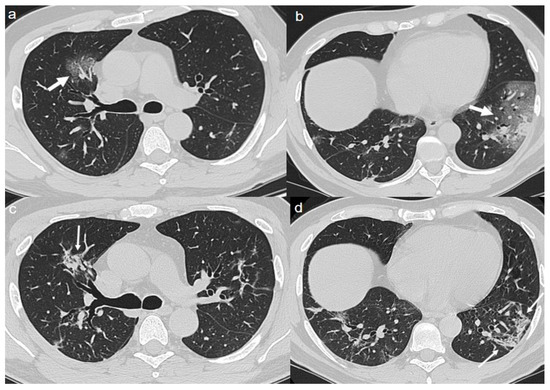

On admission, chest CT showed bilateral extensive areas of GGO and consolidations, with prevalent peripheral distribution in the upper and lower lobes (Figure 7a–c).

A CT at 4 months from the onset of symptoms showed the persistence of diffuse thickening of the interlobular septa, with fibrotic appearance (Figure 7d,e); air bubble sign with bronchiectasis (Figure 7f) was also recognizable. An air bubble sign consists of a small air-containing space that can result from a dilatation of a physiological space or from lung cystic changes or can be related to consolidation resorption.

Figure 7. (ac) CT shows bilateral extensive areas of GGO and consolidations, with prevalent peripheral distribution, in upper and lower lobes (arrows). (df) Follow up CT 4 months after admission shows persistence of diffuse thickening of the interlobular septa, with fibrotic appearance (thin arrows in d,e); air bubble sign with bronchiectasis (thin arrows in f) is recognizable.